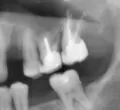

Ваши беспокойства скорее всего говорят о воспалении на верхушках корней (периодонтит).

В этом случае зуб пломбировать нельзя, Вам необходимо обратиться к лечащему врачу и объяснить Вашу проблему.